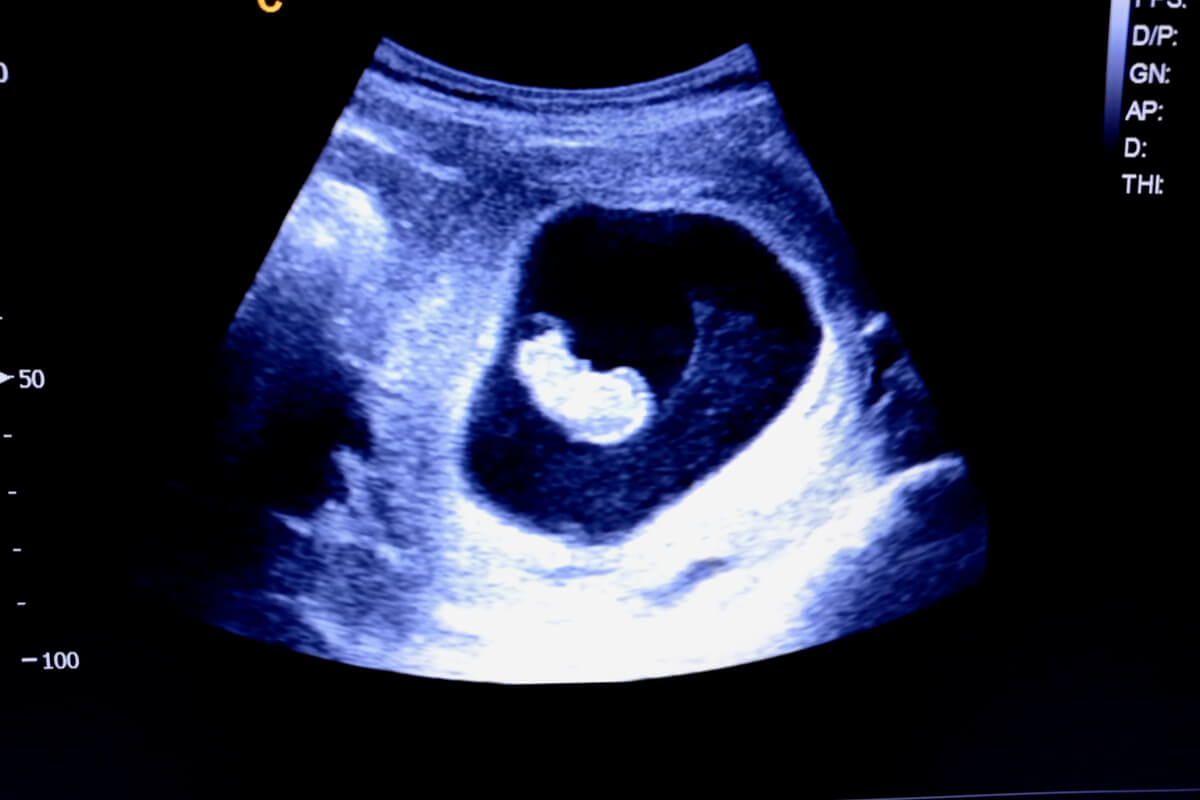

Cette stratégie permet de prédire le sexe du bébé dès la première échographie. En effet, elle se base sur la localisation du placenta et des villosités choriales dès la sixième semaine de gestation.

Pour déterminer l’emplacement du placenta, il est nécessaire que la femme enceinte subisse une échographie Doppler à partir de la sixième semaine de gestation. Vous pouvez y voir une zone lumineuse autour du sac gestationnel, qui est l’endroit où cet organe va se développer. Pour déterminer s’il est à droite ou à gauche, il faut tenir compte de l’effet miroir de cet examen.